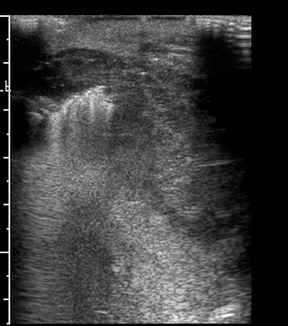

This is where the power of ultrasound diagnostics comes into play. It offers a non-invasive, precise, and reliable method to examine internal structures, providing crucial insights that can lead to early intervention and treatment.

Ultrasound diagnostics serve as a beacon of hope for individuals caught in the web of uncertainty. By offering clarity and precision, it empowers patients to take control of their health journey. Let’s delve deeper into how this diagnostic tool transformed the lives of two individuals Rohan and Aarti.